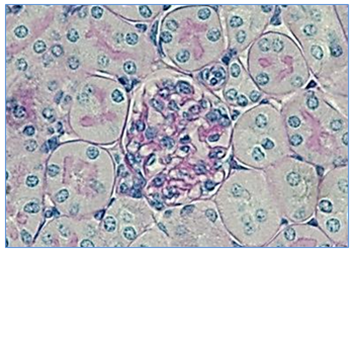

Cytométrie en flux Histologie Microscopie Pôle Analyses Cellulaires et Tissulaires *protected email* Cytométrie en flux Analyse cellulaire Tri cellulaire Clonage en plaque Imagerie en flux Logiciels d’analyse Histologie Inclusion en paraffine Coupe de tissus frais, congelés et inclus Préparation de TMA à partir de blocs de paraffine Colorations standards et spéciales, en Immunohistochimie et Immunofluorescence Numérisation des lames Microscopie électronique Microscopie Incucyte : microscope automatisé en incubateur Microscopie épifluorescence Microscopie confocale Macroscopie confocale Retraitement et analyse des images